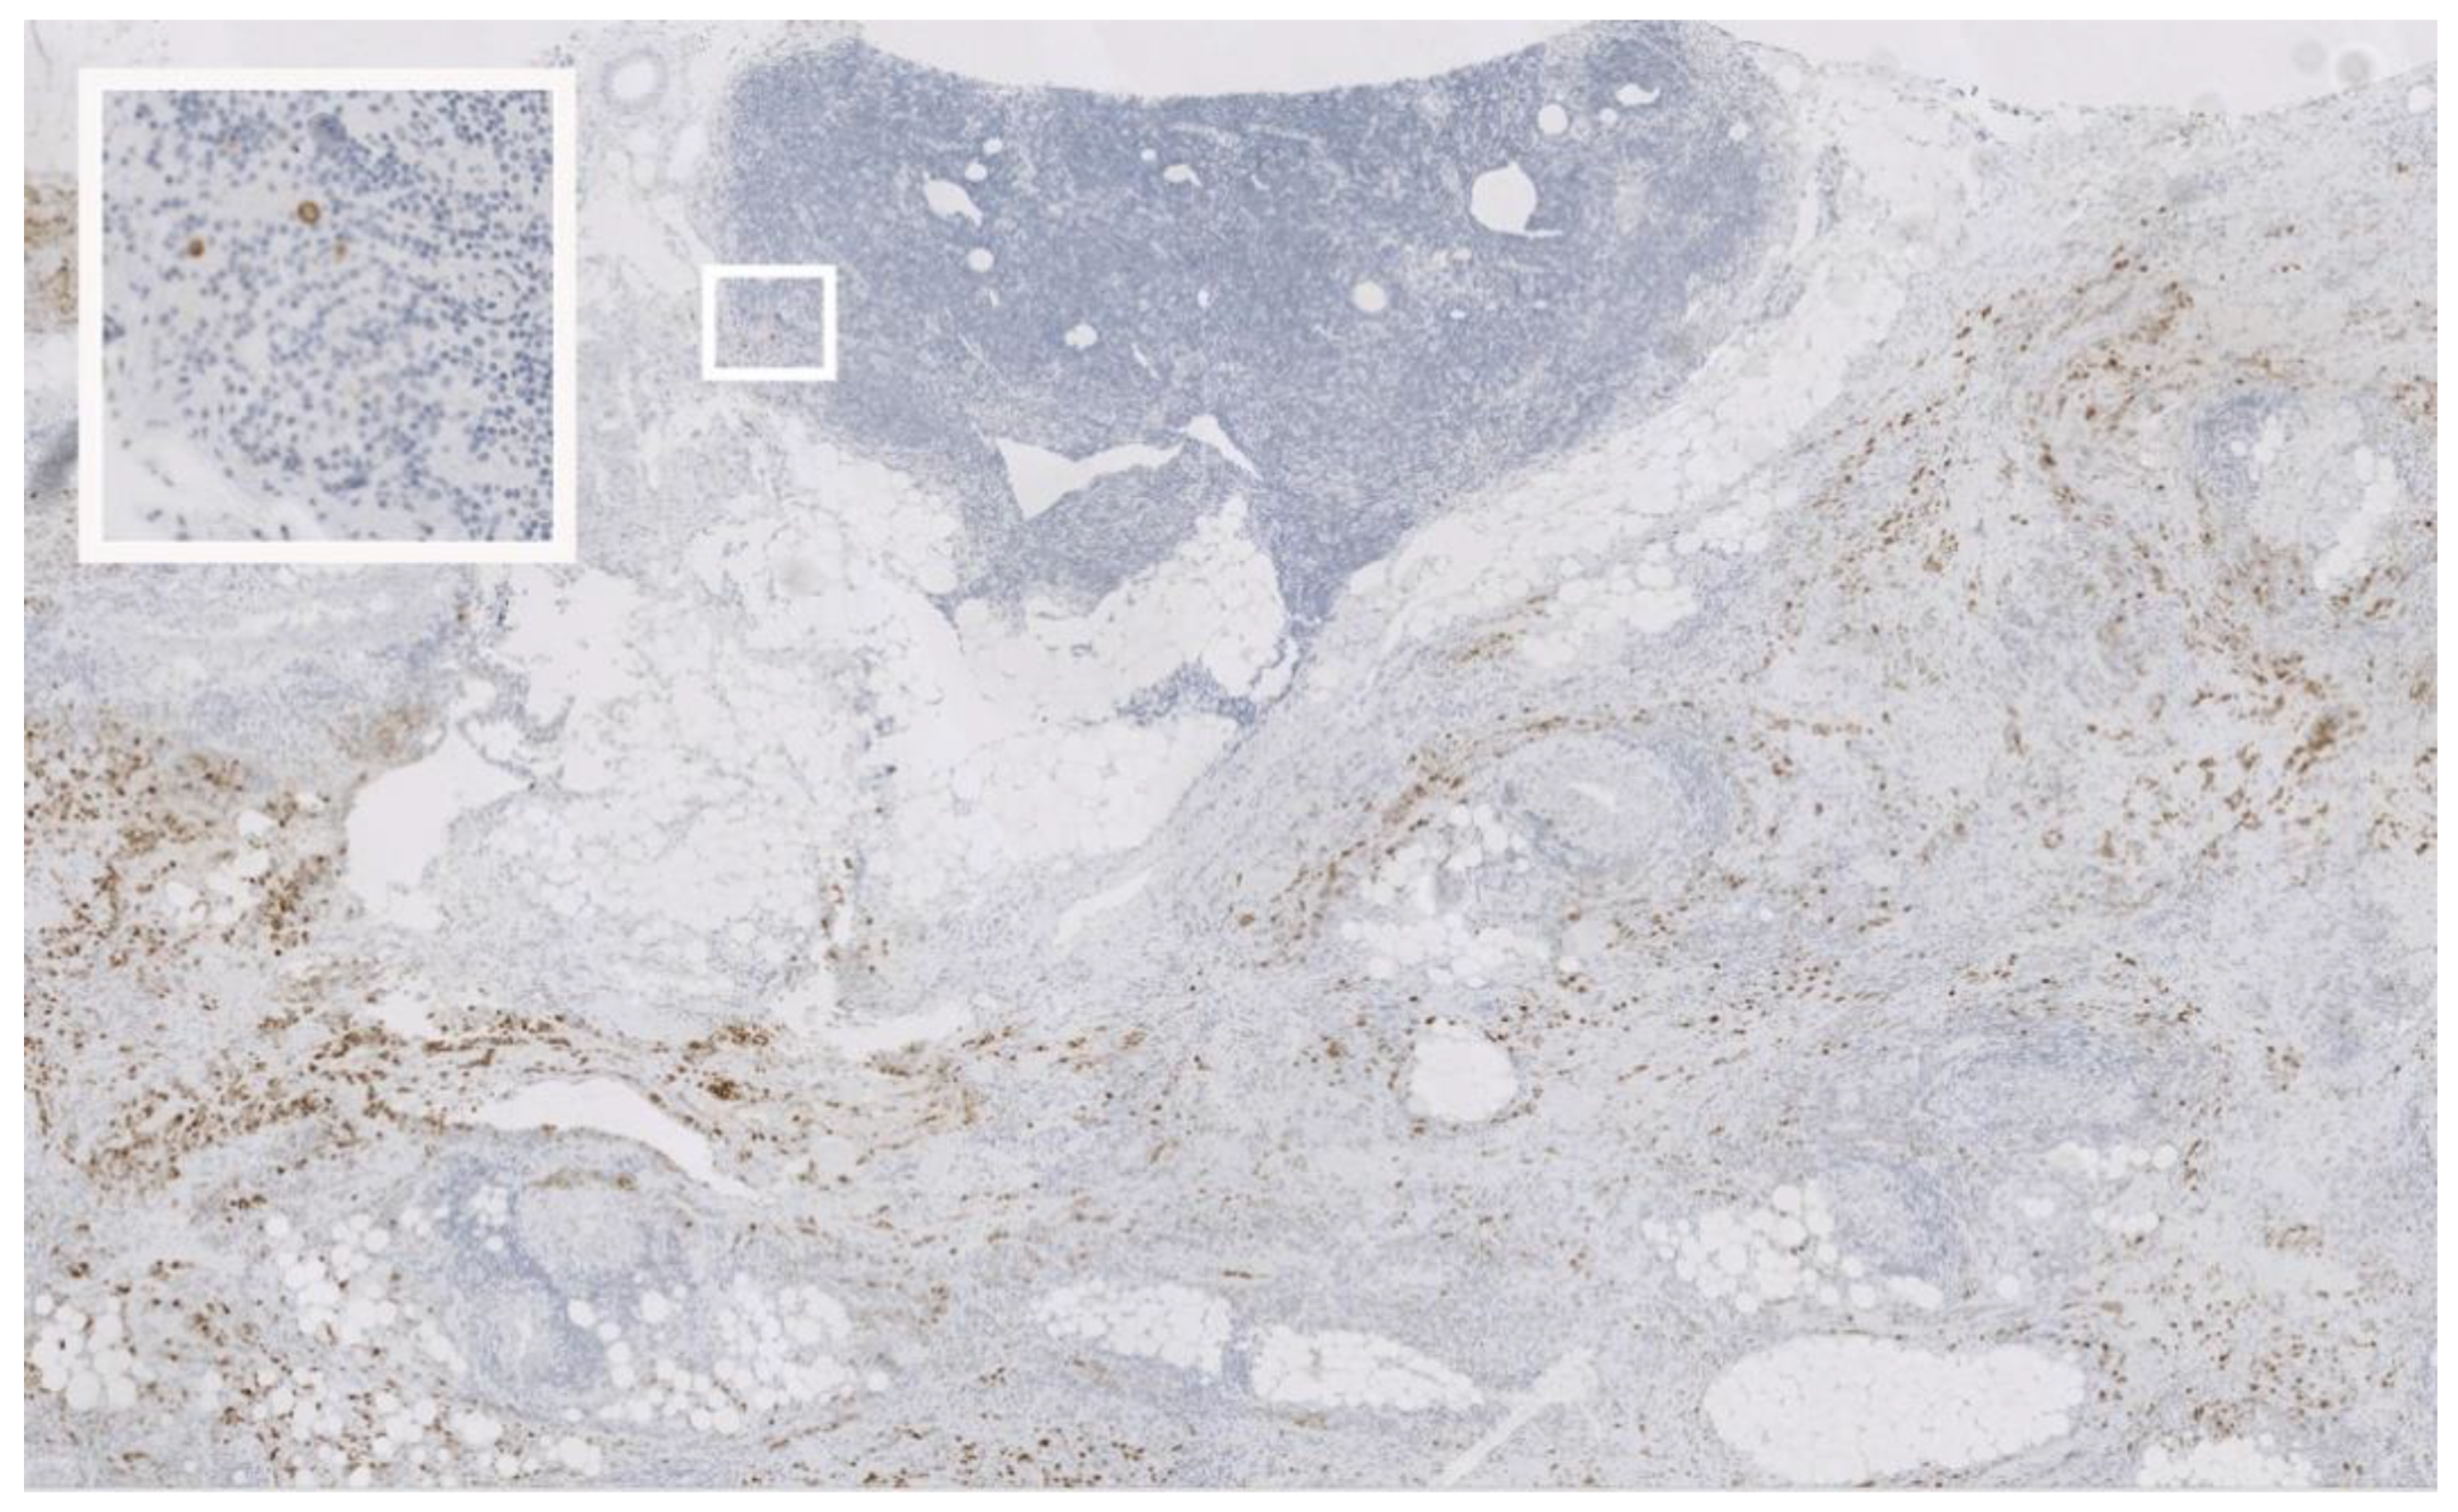

2.3. Immunohistochemistry